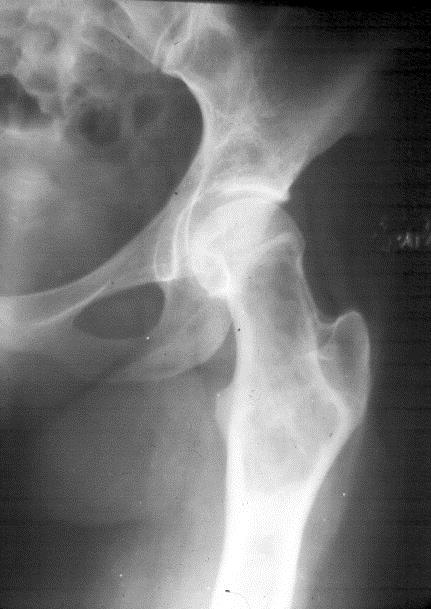

In the pelvis, proximal ends of the femura are commonly involved. Generally it is unilateral (Figure 16). In polyostotic form, involvement of the iliac and other bones is common (Figure 17). Radiologically, the head and neck of the femur are deformed and present a shepherd’s crook deformity (Figure. 18). On occasion, a cystic lesion with multiple loculations is encountered (Figure 19).

Figure 16: FD – Femur. Note the diffuse involvement.

Figure 17: FD – Polyostotic involving left iliac bone and femur.

Figure 18: FD – 8 yr old child – shepherd crook deformity of femur.

Figure 19: FD – Multiloculated appearance.